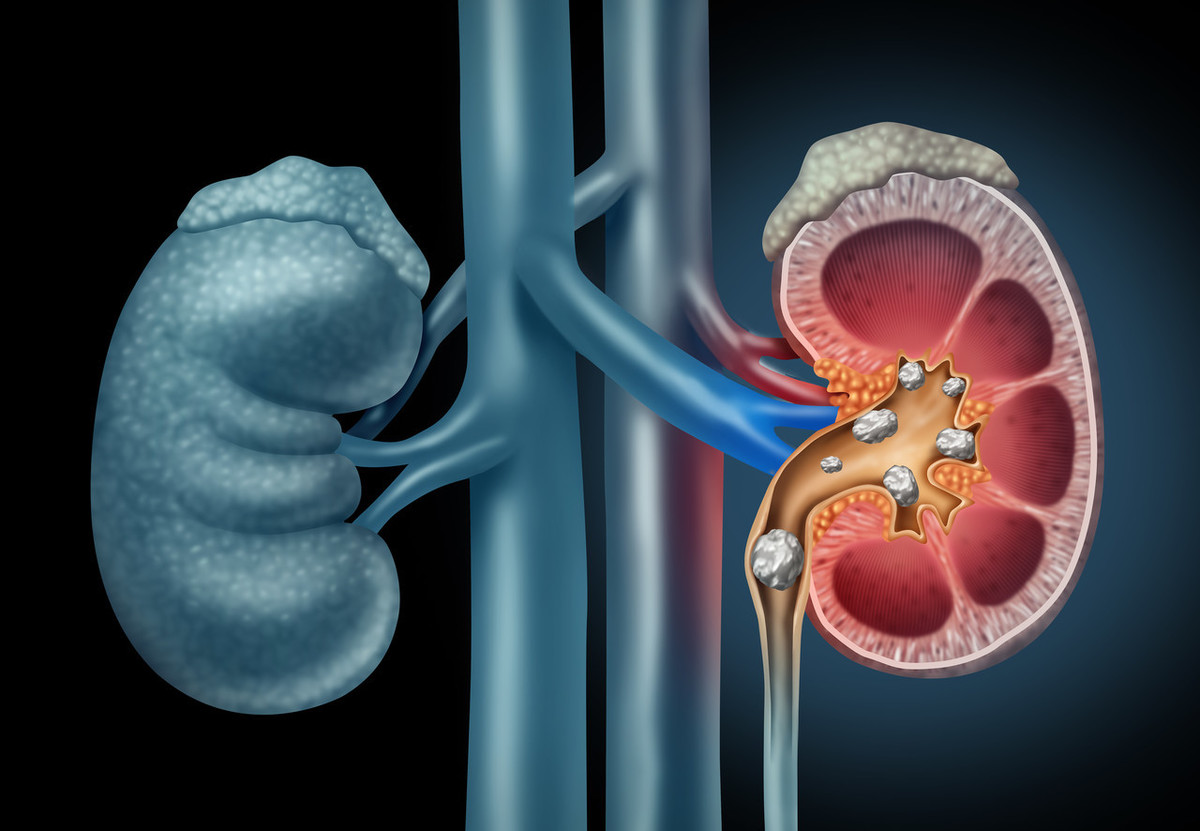

- 尿结石最佳疗法:快速缓解疼痛与饮食调理指南

-

4分钟前点击查看